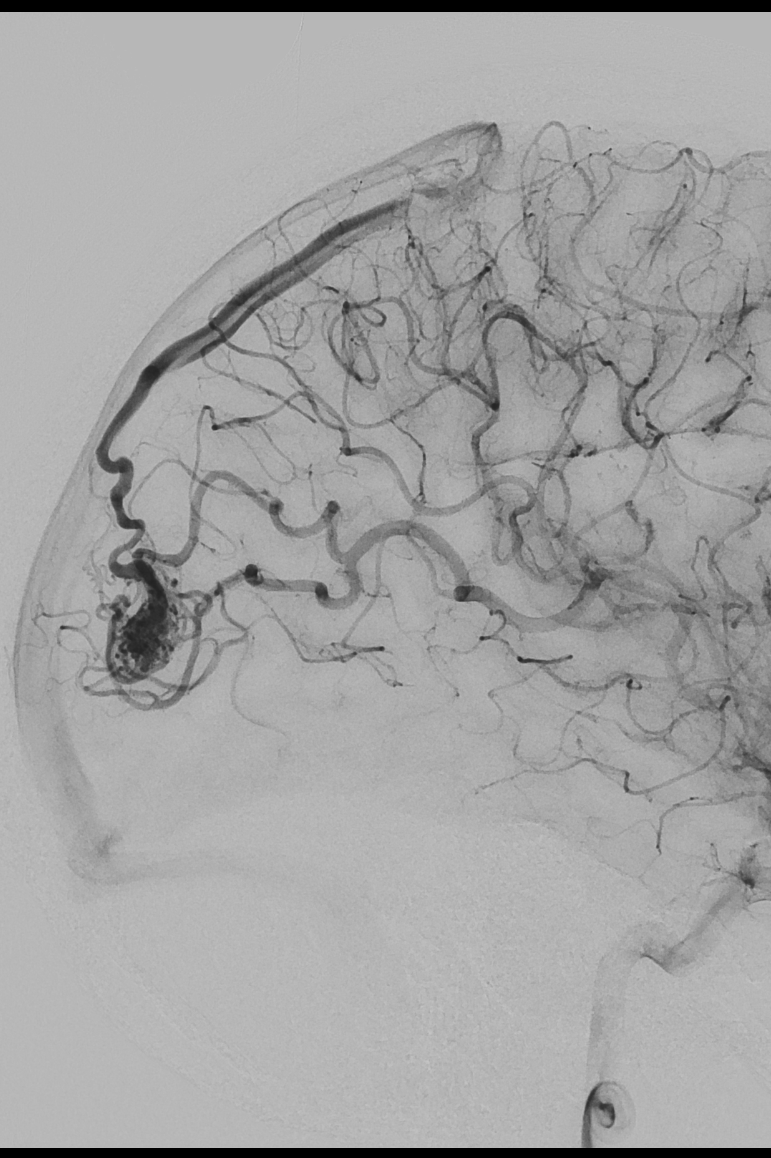

Arteriovenous Malformation

• Arteriovenous malformations are congenital vascular anomalies characterized by direct, high-flow connections between arteries and veins without an intervening capillary bed, leading to chronic hemodynamic stress on fragile vessels. Their development and clinical behavior are shaped by genetic susceptibility, aberrant angiogenic signaling, somatic mutations, and local inflammatory and biomechanical factors. Research in this field aims to elucidate the molecular and cellular mechanisms driving AVM formation, progression, and rupture; identify biomarkers and imaging features that predict hemorrhage risk; and optimize microsurgical, endovascular, and radiosurgical strategies to reduce bleeding risk and improve long-term neurological outcomes.